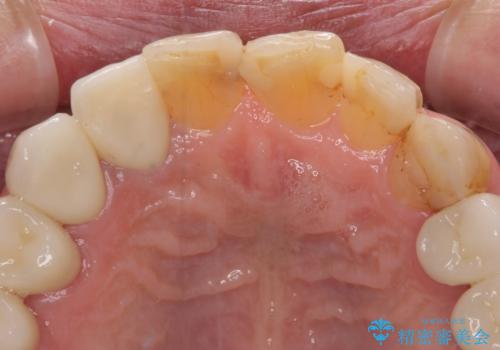

- 前歯のデコボコや、奥歯を咬んだときに痛みがあるとのことで来院された患者様です。

全体的に問題が多く、全てをしっかりと治療したいとのことでした。

全体的に中等度の歯周病と診断されたため、歯周外科処置やインプラントによる咬合回復から進めて行き、矯正治療による歯列改善を行った後にオールセラミッククラウンにて補綴することとしました。

矯正治療を希望して来院されましたが、歯周病を併発していたため、矯正治療開始前の処置が非常に多くなりました。特に歯槽骨の再生治療を行ったため、外科処置後の静置期間が長くなり、4年弱の治療期間となりました。

治療後には咬みやすさだけでなく、前歯が大変審美的に仕上がり、患者様には大変満足していただきました。